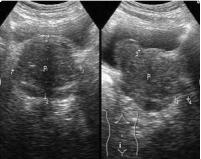

彩超:是简单、无痛苦的前列腺检查手段,可以发现前列腺有无增生。经直肠探头的超声检查图像清晰,结果准确,较体外超声检查更胜一筹。但是彩超检查前列腺主要作用就是诊断前列腺增生。这也是其最大的价值。彩超不能诊断前列腺炎,常规超声也不能确诊前列腺癌。

比如经直肠前列腺,可以看的很清楚,内腺,外腺都可以测量大小,对内部长出的一些结节可以看的到,但是不能定性,因为不管是炎症,增生,肿瘤,声像图上看起来都差不多,很难辨别。

所以前列腺彩超的主要作用是测量前列腺的大小,再结合个人症状,诊断前列腺增生。